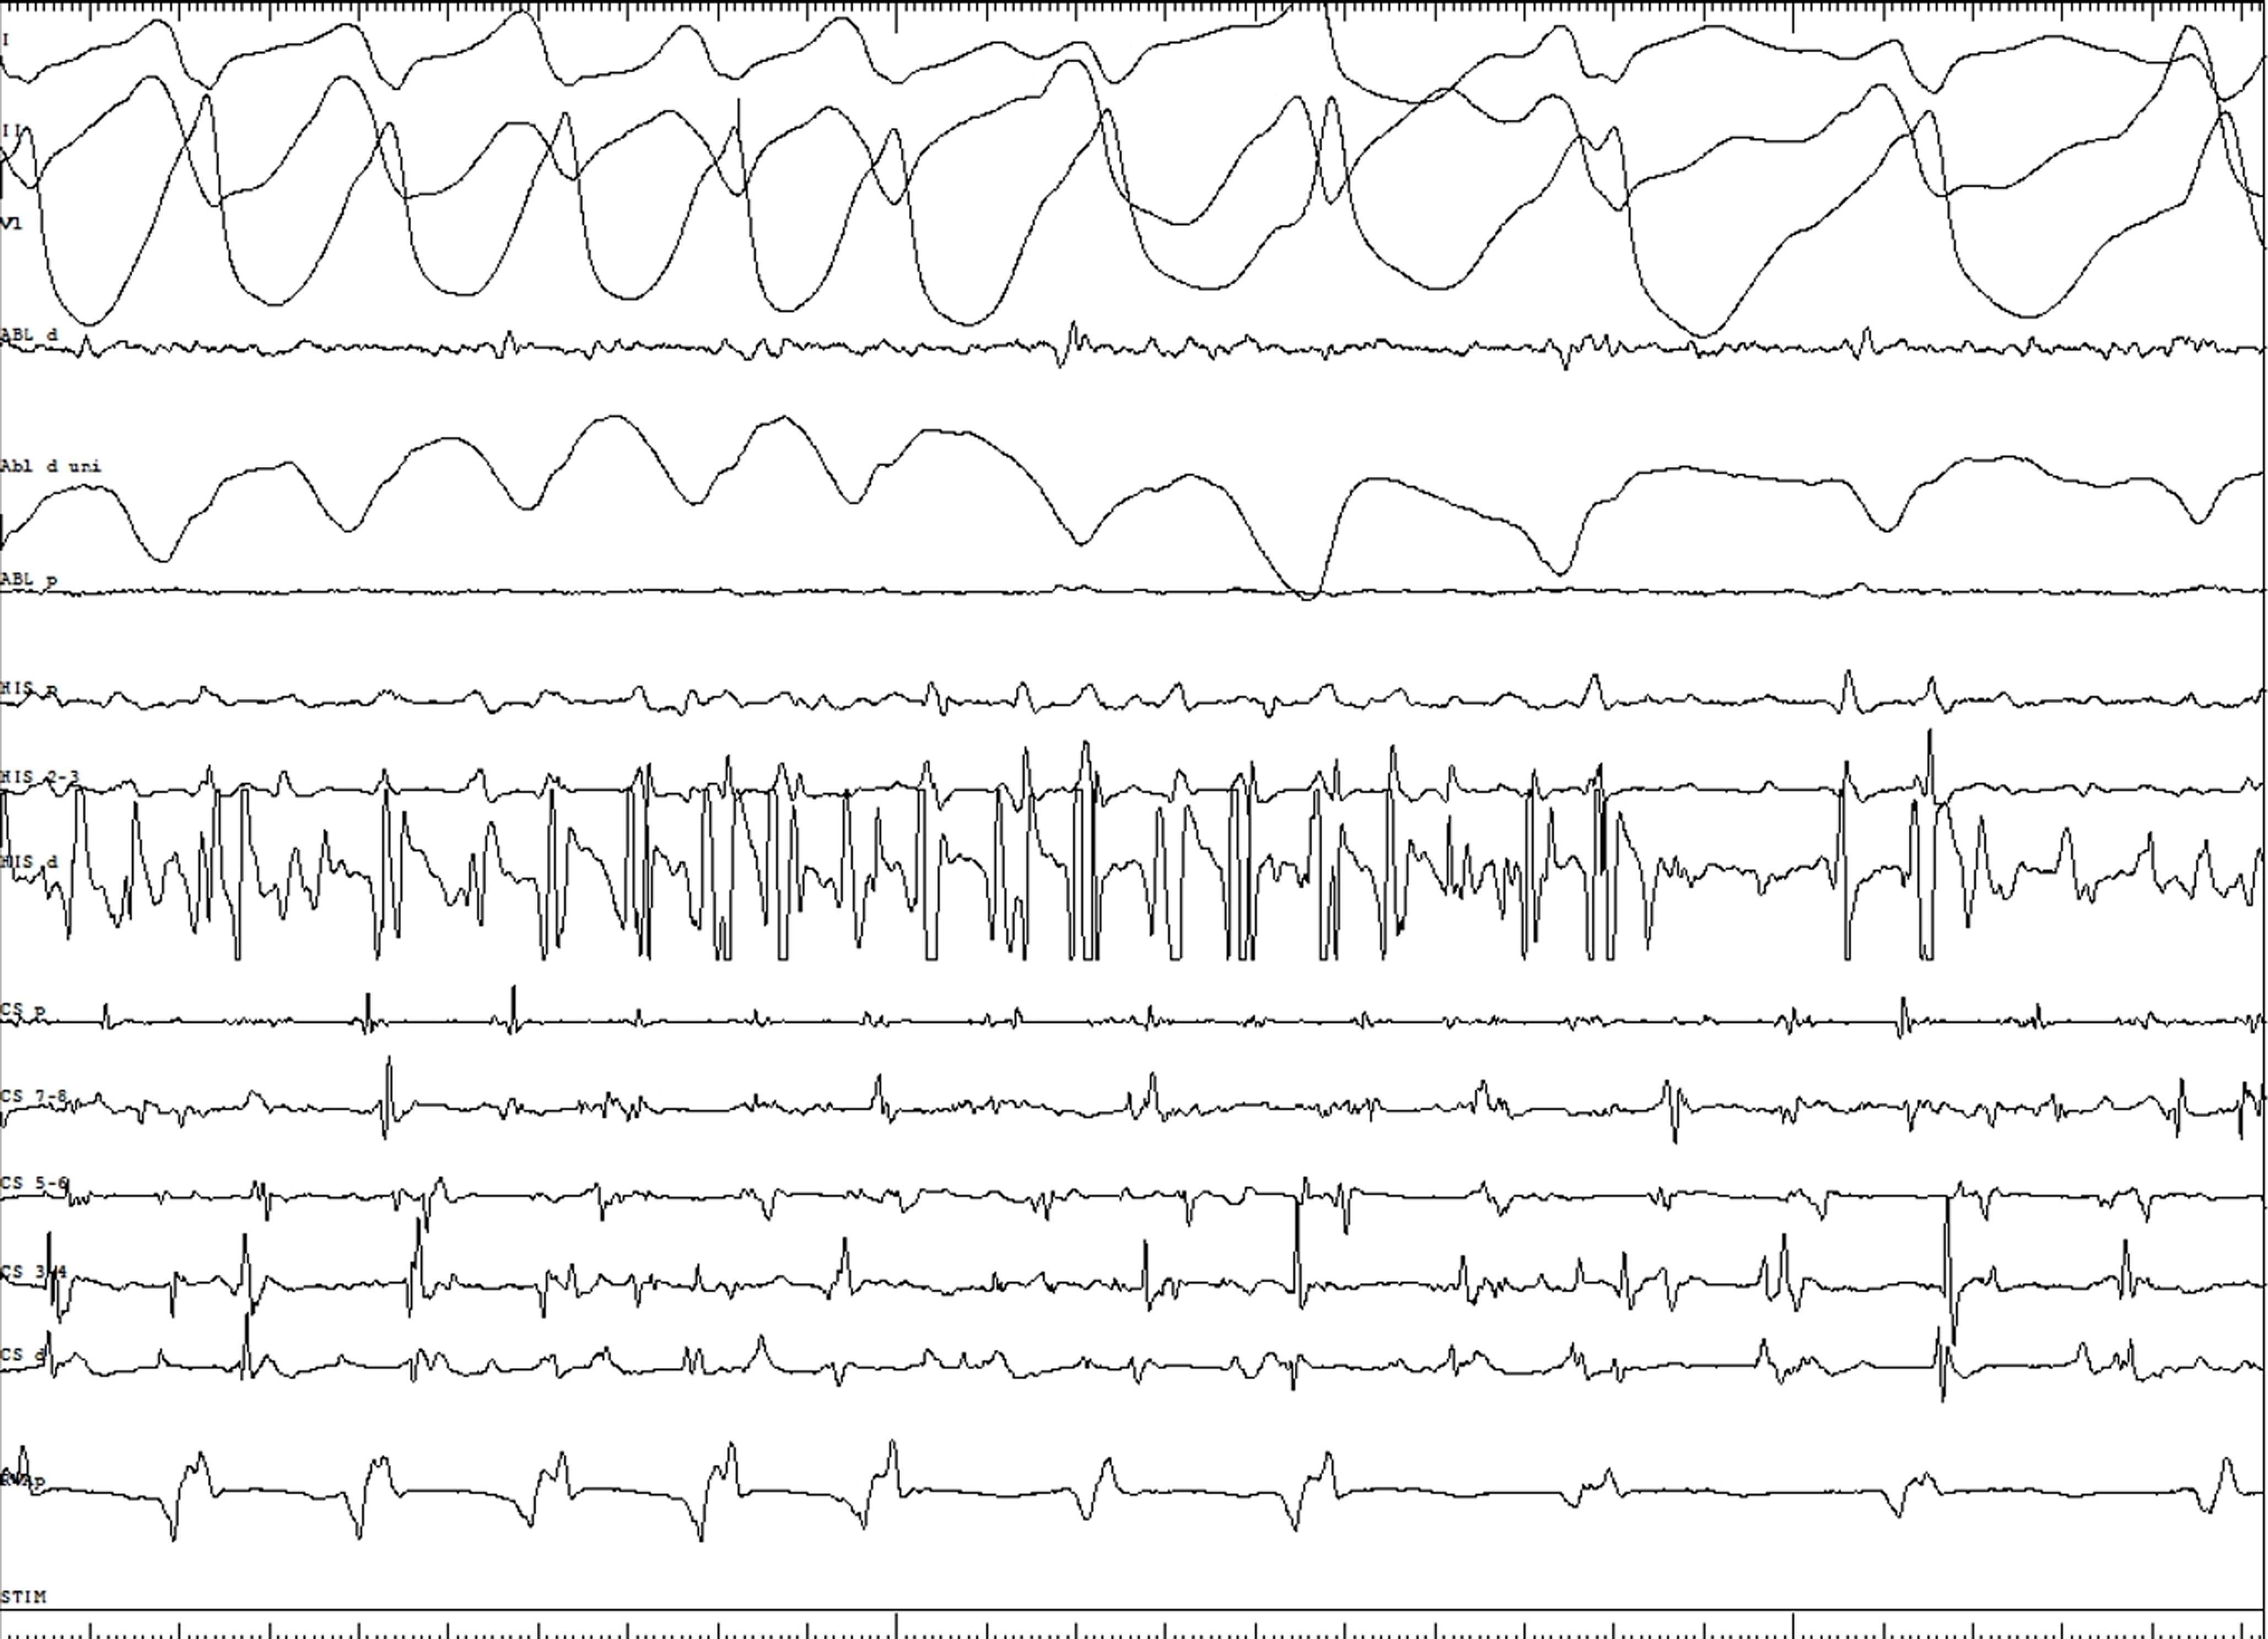

A 17-year-old girl presented with palpitations and Wolff–Parkinson–White pattern on electrocardiogram (Figure 1). Her echocardiogram was suggestive of left ventricular non-compaction with preserved ejection fraction (Figure 2A, Video 1). This was confirmed on cardiac magnetic resonance imaging per criteria proposed by Petersen et al (Figure 2B, Video 2).Reference Petersen, Selvanayagam and Wiesmann7 She underwent an exercise stress test during which pre-excitation persisted at a peak heart rate of 171 beats per minute suggesting a possible high-risk pathway. She subsequently underwent an electrophysiology study during which orthodromic reentrant tachycardia was induced (cycle length of 460 msec) with programmed atrial stimulation. On decremental atrial pacing, the accessory pathway block cycle length was < 200 milliseconds and the shortest preexcited RR interval during atrial fibrillation measured 174 msec (Figure 3), findings which confirmed the pathway to be high risk. The episode of atrial fibrillation resulted in haemodynamic instability and required immediate cardioversion. Mapping was therefore only performed during pre-excited sinus rhythm. Earliest ventricular activation during sinus rhythm was noted over a broad area in mid coronary sinus and superolateral mitral annulus. However, application of radiofrequency energy at these sites was not successful in eliminating pre-excitation (Figure 4). She was started on sotalol until she underwent another EP study a month later. This time, the earliest ventricular activation during sinus rhythm was recorded over a broad area located from 2 to 4 o’clock along the mitral valve annulus. Empiric radiofrequency ablation was performed at the site. Orthodromic reentrant tachycardia was induced following initial ablations (Figure 5A), but no tachycardia could be induced following consolidation of the site. No ventriculoatrial conduction was noted following consolidation. Anterograde accessory pathway conduction, however, persisted, but antegrade pathway block occurred at an atrial pacing cycle length of 450 msec suggesting that the pathway had been modified. Eighteen months following the second ablation, the patient presented to the emergency department in supraventricular tachycardia, which was terminated with adenosine (Figure 5B). She is currently treated with flecainide 75 mg twice daily and is doing well.

Figure 3. Shortest preexcited RR interval during atrial fibrillation measures 174 msec suggesting a high-risk pathway.